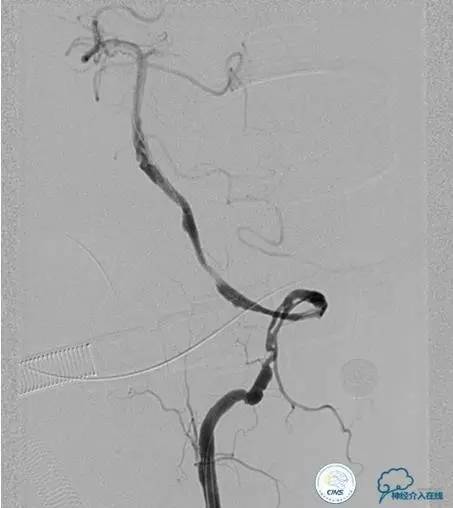

▼开通

出院情况:头晕症状消失,构音障碍缓解,进食无呛咳,饮水实验(-),右侧肢体远端肌力恢复到Ⅰ级。